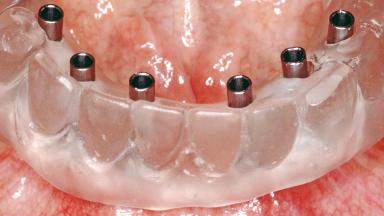

A 68-year-old, completely edentulous male patient presented for evaluation and treatment options. He reported excellent general health and was taking no regular medication. He had been edentulous for approximately 12 years, having lost his teeth to periodontal disease and dental caries. The patient’s chief complaint was incompetent function. His secondary concerns included his appearance and the desire for a predictable outcome. He attributed his reduced functional capacity to his lower complete denture, which he described as poor. He was particularly concerned with the denture’s instability and poor fit. In general terms, he was satisfied with the maxillary complete prosthesis. The maxillary prosthesis was characterized by adequate retention, stability, and support, although the fit was considered less than ideal.